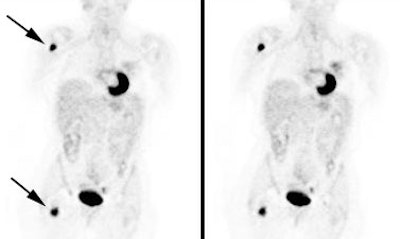

|

Change in stage: The patient below was felt to have Stage IIIB disease based upon the chest CT findings. FDG PET imaging confirmed ipsi- and contralateral mediastinal adenopathy, but also reveal a left scapular metastasis (seen retrospectively on the CT scan [white arrow]). A left iliac metastasis was also identified (black arrow right PET image). This resulted in a change in patient stage as the patient was now has Stage IV disease. |